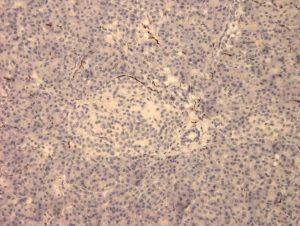

CAT NO: ABS 023-02 | Application: ELISA, WB, IHC, IF